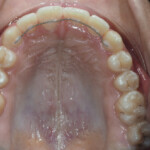

Before Transformation!